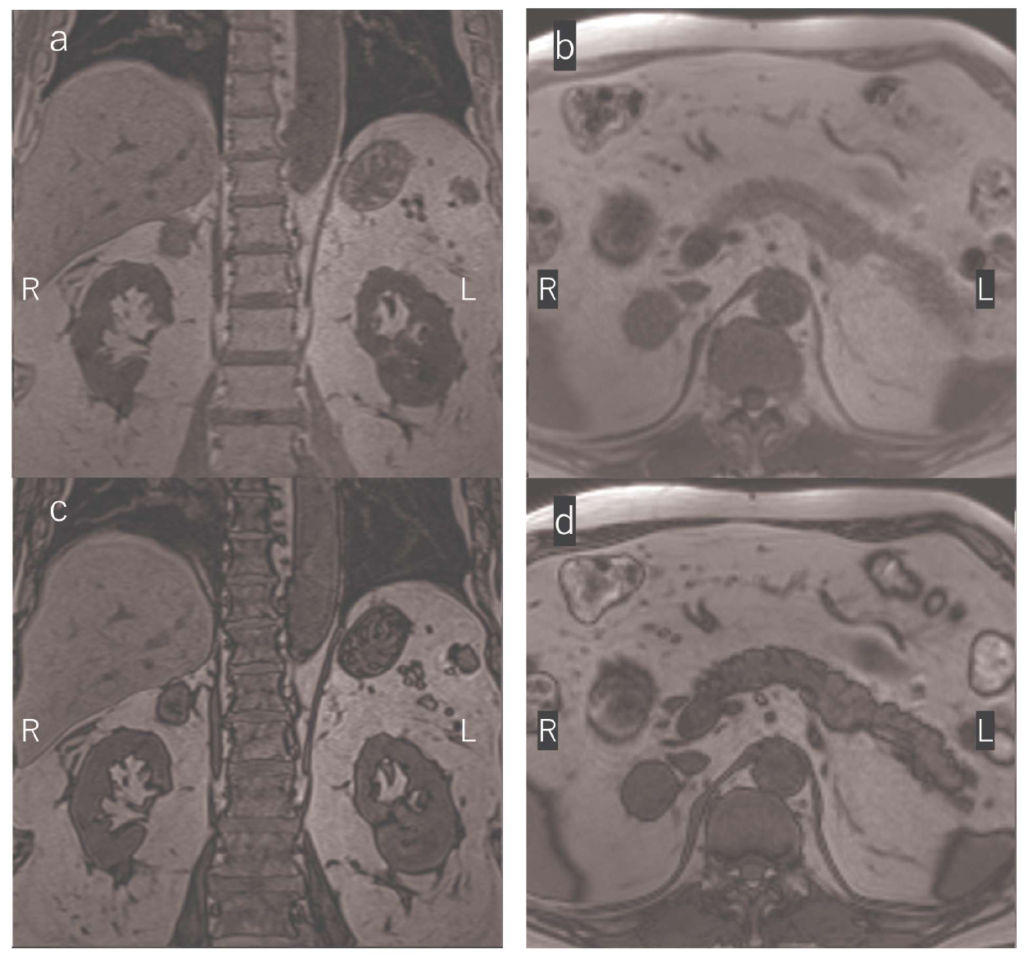

問題 40 T1強調像の冠状断像と横断像のin phase(a,b)とopposed phase(c,d)を示す。疑われる疾患はどれか。

1. 副腎嚢胞

2. 褐色細胞腫

3. 膵頭部がん

4. 副腎皮質がん

5. クッシング症候群